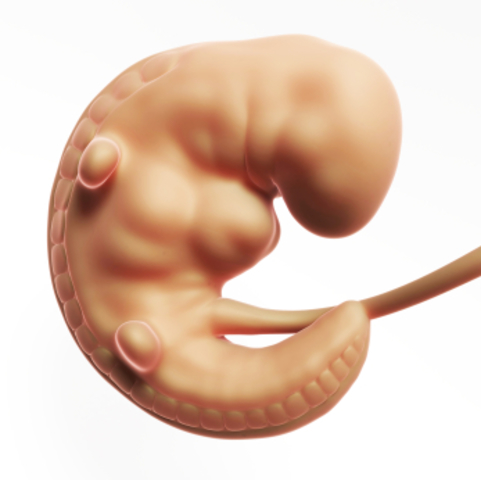

• Semana 3

Semana 3

Se forma el tubo neuronal y comienza a apreciarse una extremidad abultada: la cabeza. Se desarrollan las primeras células nerviosas

Nacen células que dan impulsos eléctricos lo que hace que tenga sus primeros latidos y el cerebro.

• Semana 4

Semana 4

Principia el desarrollo de los ojos, de los oídos, de la boca y de la nariz. Se observan los brotes que van a dar origen a los brazos y a las piernas. La prominencia cardíaca es muy visible. Se desarrollan las vesículas cerebrales